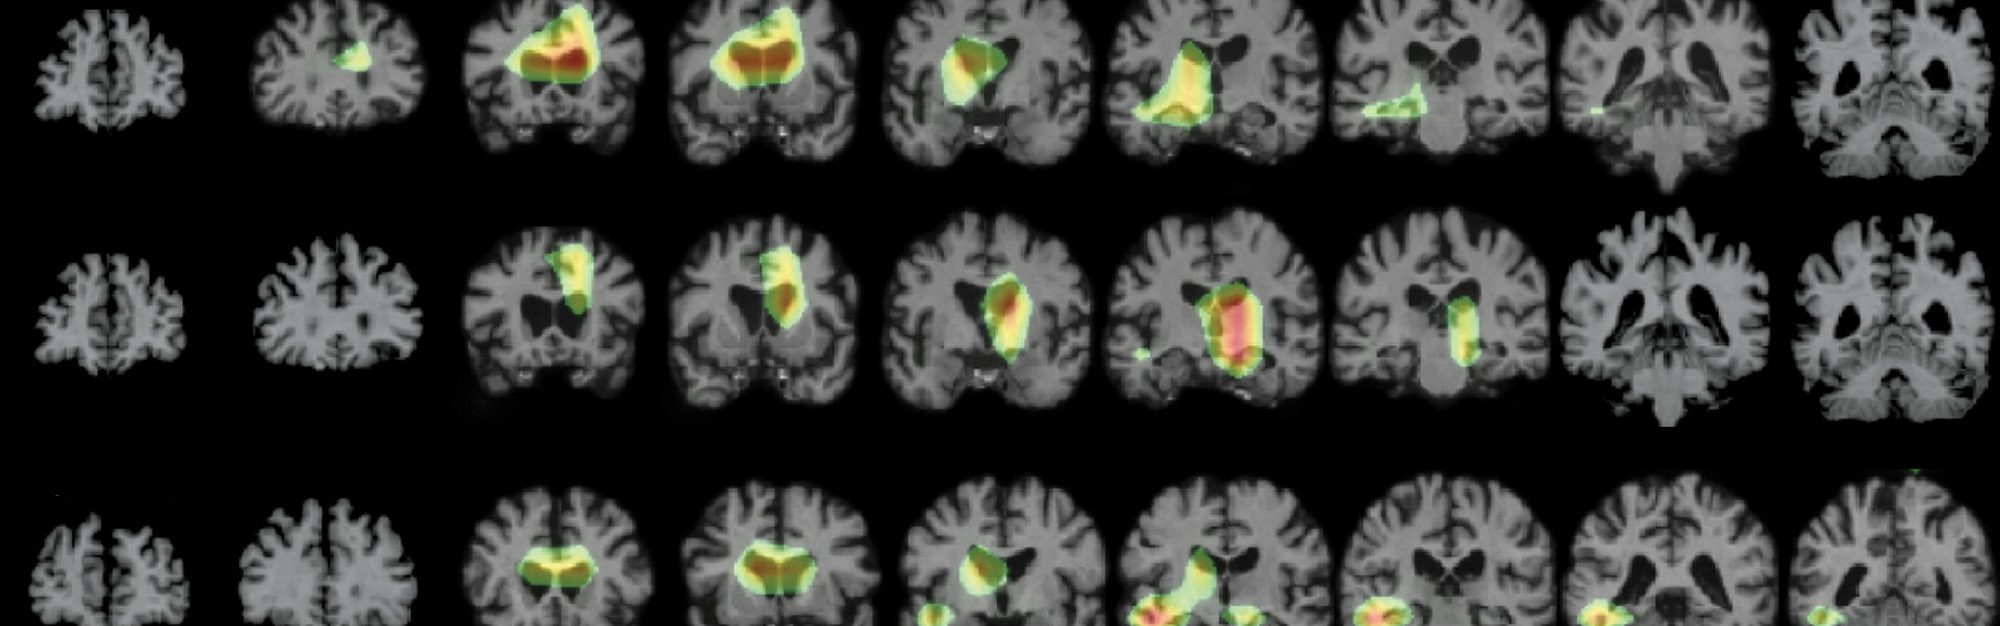

MRI imaging of brains.